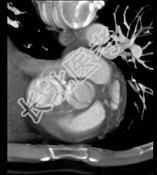

- 单项选择题下面一组图像考虑为 ( )

A、正常的肺动脉瓣

B、正常的二尖瓣

C、正常的三尖瓣

D、正常的主动脉瓣

E、变异的主动脉瓣(两个瓣膜)